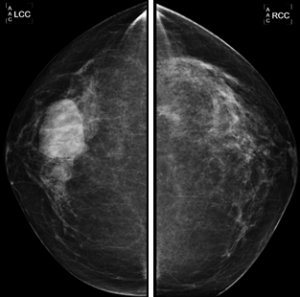

Las mamografías diagnósticas se realizan en mujeres con más de 30 años o cuando existe alto riesgo de enfermedad mamaria. La ecografía estaría más indicada en mujeres menores de 30 años.

Imágenes de la mamografía: